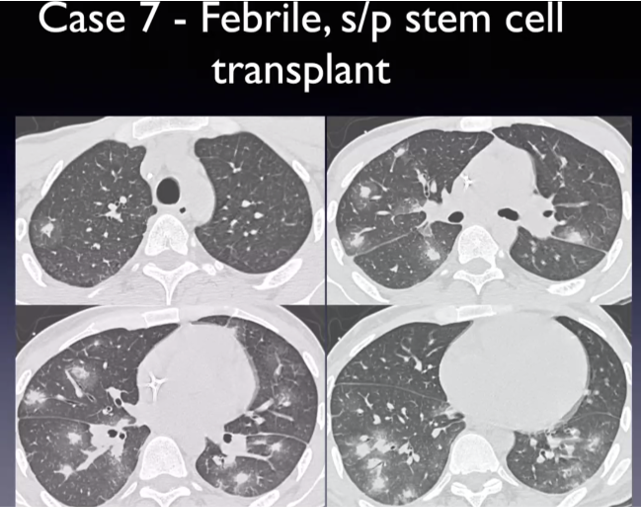

expiratory HRCT images

Diffuse idiopathic neuroendocrine cell hyperplasia (DIPNECH)

multiple small pulmonary nodules and mosaic attenuating from air trapping due to constrictive bronchiolitis

bronchiolar inflammation

Ritalin lung can look like this too